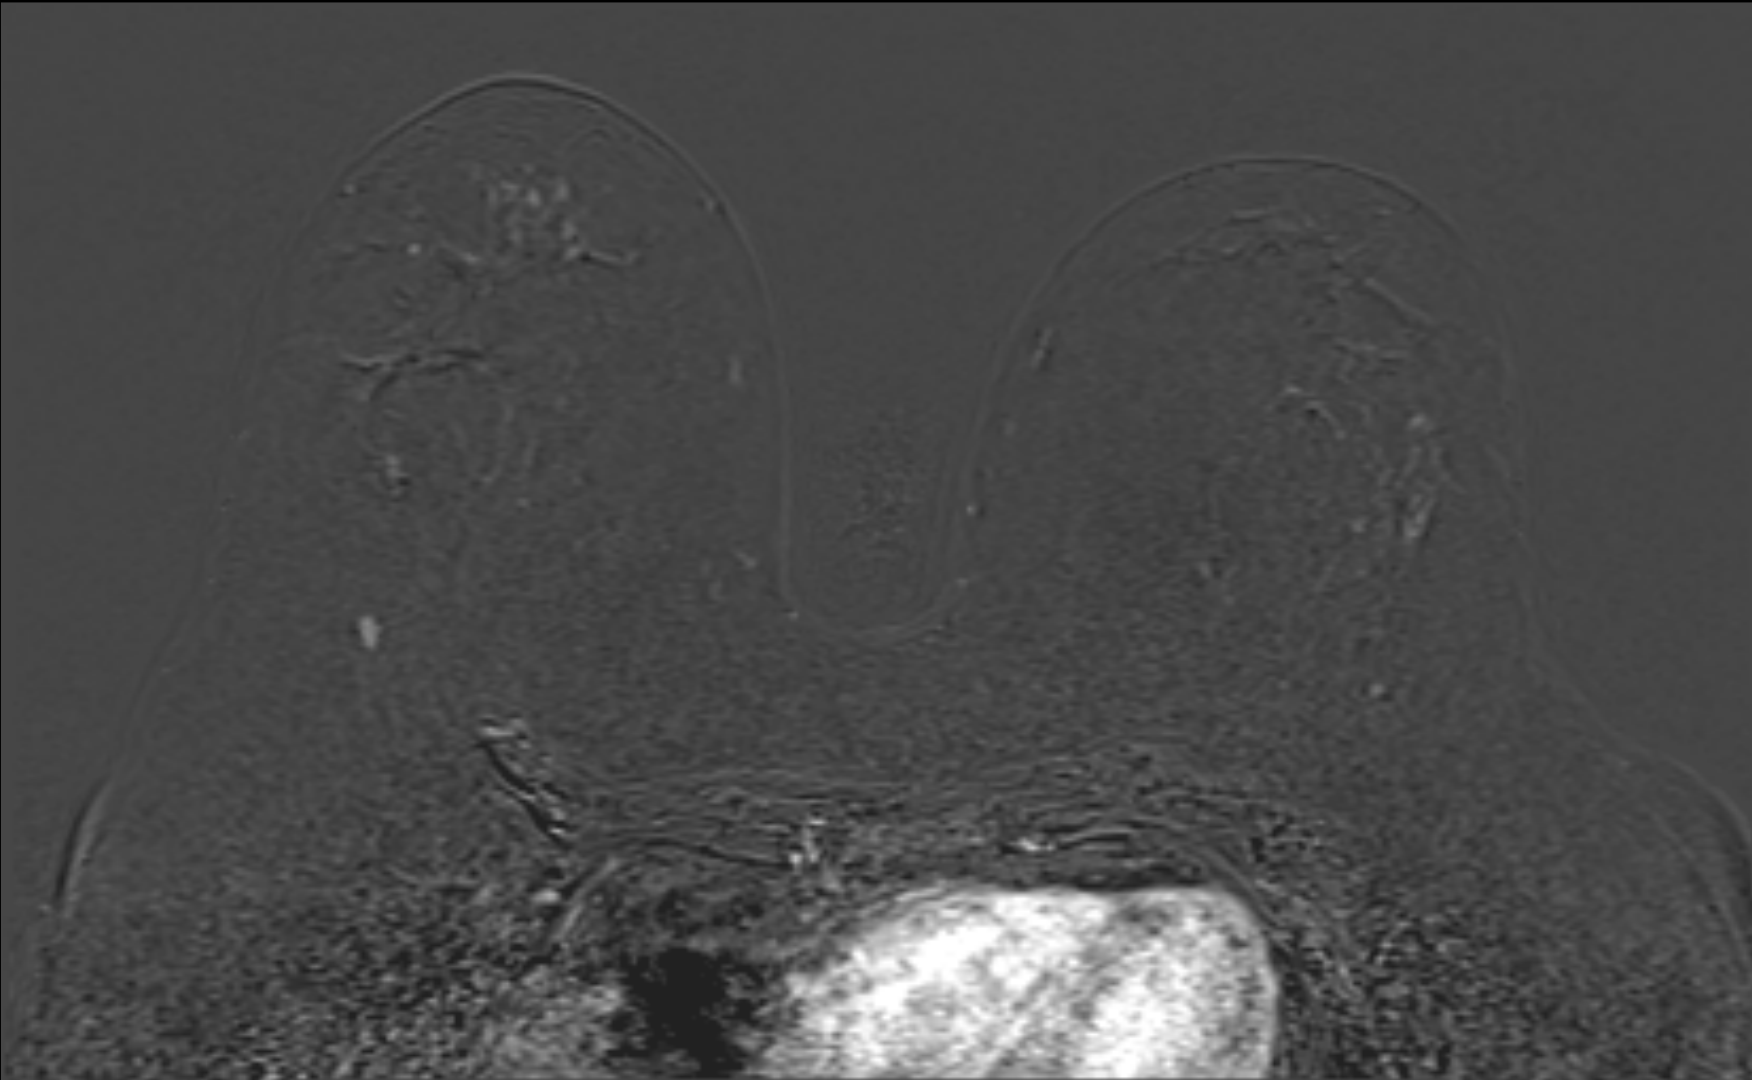

RM_mama_B4

Ressonância magnética das mamas com contraste. Observa-se nódulo oval, de margens circunscritas, apresentando realce homogêneo após contraste, com curva cinética do tipo washout. Localiza-se no quadrante inferolateral da mama direita, medindo cerca de 1,0 cm. Apesar da morfologia relativamente benigna, o padrão cinético suspeito reforça a classificação como BI-RADS® 4.